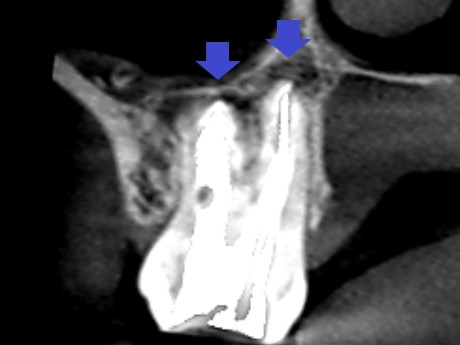

精密根管治療2年後の患部の矢状断のCT画像です。第三大臼歯に達していた大きな膿が消失し歯槽骨が再生しています。

精密根管治療2年後の患部の冠状断のCT画像です。根の先を覆っていた全ての膿が消失し歯槽骨が再生しています。